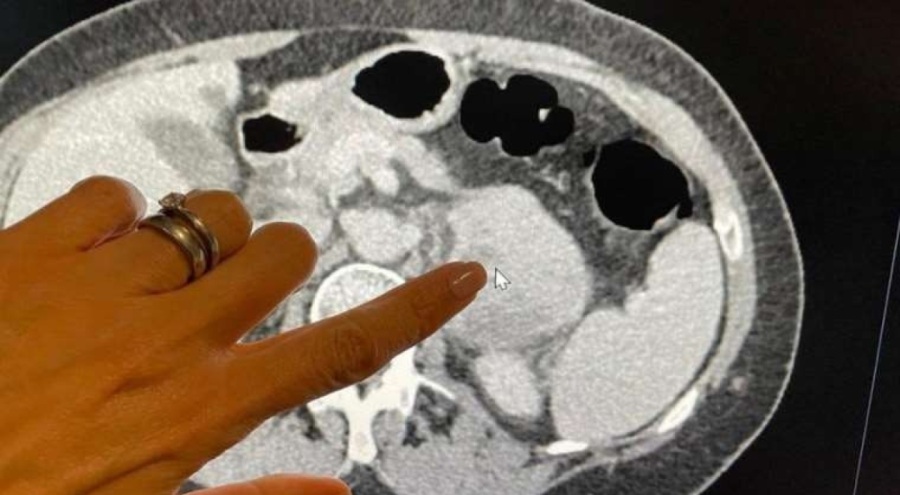

Tıp dergisi Lancet Onkoloji'de yayımlanan araştırmada, adlı, karın bölgesinin arkasında gelişen ve nadir görülen bir kanser türü olan retroperitoneal sarkom bulunan 170 hastanın görüntülemelerinde, gözle görülemeyen işaretleri bulmak için radyomiks adlı bir teknik kullanıldı.

Diş hemşiresi Tina McLaughlan'a geçen yıl Haziran'da karın bölgesinin arkasındaki sarkom nedeniyle çektiği karın ağrılarının ardından, doktorlar sorunu tespit edebilmek için bilgisayarlı tomografi (CT) yöntemini kullandı.